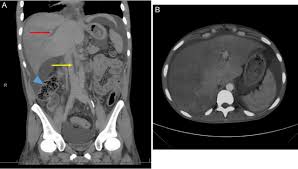

Coin in the Esophagus. Thrombosis of the cerebral splenic portal hepatic renal subclavian and retinal veins and of the inferior vena cava. Carcinoid Tumor of Small Bowel.

Chiasmata -mə-tə or chiasmas also chiasms 1. Esophageal varices are extremely dilated sub-mucosal veins in the lower third of the esophagus. Located in metro Denver northern Colorado and western Nebraska serving all of the Front Range our team consists of board-certified and fellowship-trained interventional radiologists. This results in hepatic congestion similar to Budd-Chiari syndrome and post-sinusoidal portal hypertension. The patients condition should be monitored throughout the procedure. They are most often a consequence of portal hypertension commonly due to cirrhosis. Toxic injury to liver sinusoids causes sloughing of endothelial cells that embolize to hepatic venules and cause eventual fibrosis of the venules. Coin in the Esophagus. There is no clear consensus regarding the number of occluded veins some authors claim that there should be at least one occluded hepatic vein 7 others state that there are no significant.

Carcinoma of the Colon. Budd-Chiari syndrome a blockage in one or more veins that carry blood from the liver back to the heart. And coumarin skin necrosis adrenal gland hemorrhage and infarction. Toxic injury to liver sinusoids causes sloughing of endothelial cells that embolize to hepatic venules and cause eventual fibrosis of the venules. Chiari malformation CM is a structural defect in the cerebellum characterized by a downward displacement of one or both cerebellar tonsils through the foramen magnum the opening at the base of the skull. Embolism and thrombosis of. La présence dune ou plusieurs affections prothrombotiques est fréquente La prise en charge repose sur un traitement anticoagulant précoce le traitement de l.